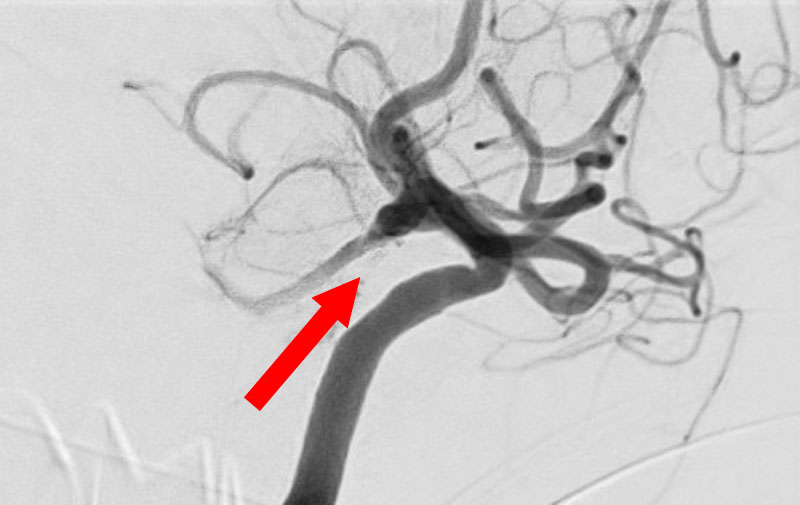

No.1630 手術前